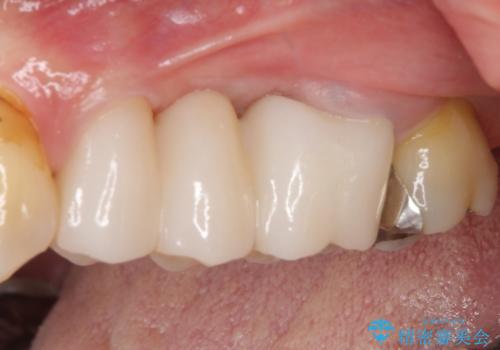

ものが挟まる原因は、保存困難なほど歯肉から露出していた歯根にあったため、抜根することで気になっていた問題は解消されました。

外観も審美的になり、患者様には大変満足していただきました。